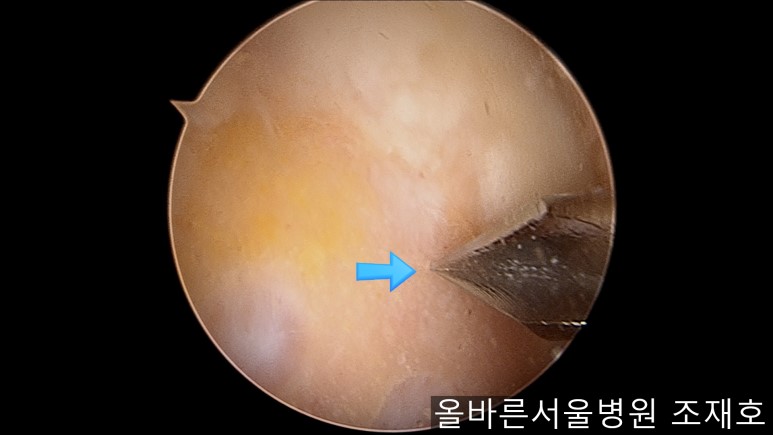

用水冲洗清理空间,为注入CARTISTEM做准备。

以注射的方式将CARTISTEM填满每一个孔。

填充完每个孔后将剩余的CARTISTEM涂抹在孔上方。